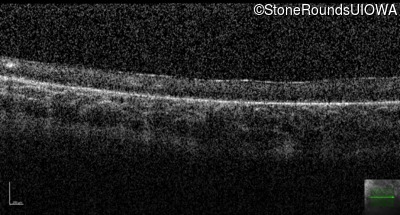

Optical Coherence Tomography - Left - Hand Motion 6" sc

Exemplar / OCT Stack

OCT Stack